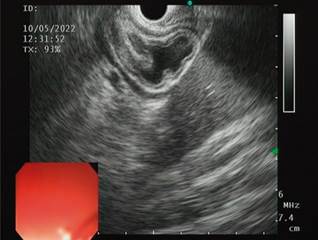

The possibility of ERCP by laparoscopic transgastric enteroscopy and EUS-directed transgastric ERCP (EDGE) is analyzed (Figure 2).

Given the background in the literature and our experience, which reveals a high risk of failed enteroscopy procedures associated with the length of the alimentary loop, we decided to rule out this option.

The possibility of a laparoscopic approach is discussed, which is not imperative since the patient has had a cholecystectomy. It is also considered that the patient does not want new surgical interventions or their inherent risks. We then opted for EUS-directed management since, during the diagnostic EUS, the accessibility of the remnant stomach was verified in the proximity of the gastric reservoir and the afferent loop (Figure 3).